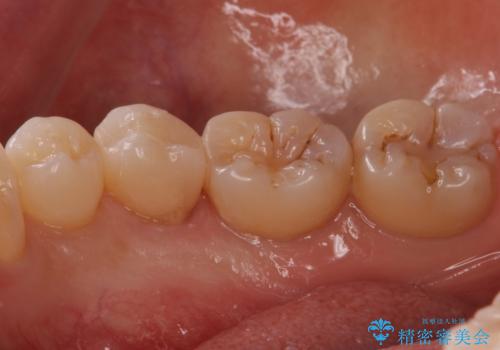

歯と歯の間の虫歯 セラミックインレーでの修復処置

- 検査の結果、歯と歯の間に虫歯が確認された患者様です。

虫歯を除去した後、セラミックインレーで修復処置を行います。

- 右下5 セラミックインレー 77,000円費用は治療当時の料金となります

レントゲン画像では写りにくい小さな虫歯も発見したため、そこも含めた形での修復処置を行いました。